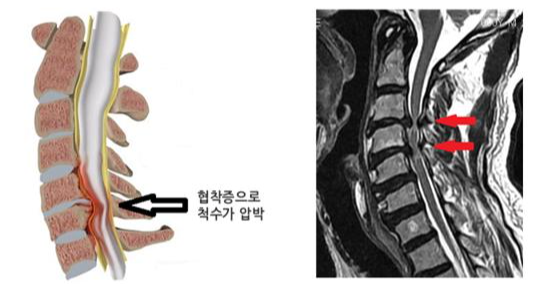

증상의 심각성과 조합은 개인마다 크게 다를 수 있다는 점에 유의하는 것이 중요합니다. 어떤 사람들은 가벼운 불편함을 느낄 수도 있고, 다른 사람들은 쇠약해지는 통증과 심각한 기능 상실을 겪을 수도 있습니다. 더욱이, 드물지만, 경추 추간판 탈출증이 척수를 압박할 만큼 커지면 경추 추간판 탈출증이 경추 척수병증과 같은 더 심각한 상태로 이어질 수 있으며, 협응 장애, 보행 장애, 극단적인 경우에는 자세 변화 등의 증상이 나타날 수 있습니다.